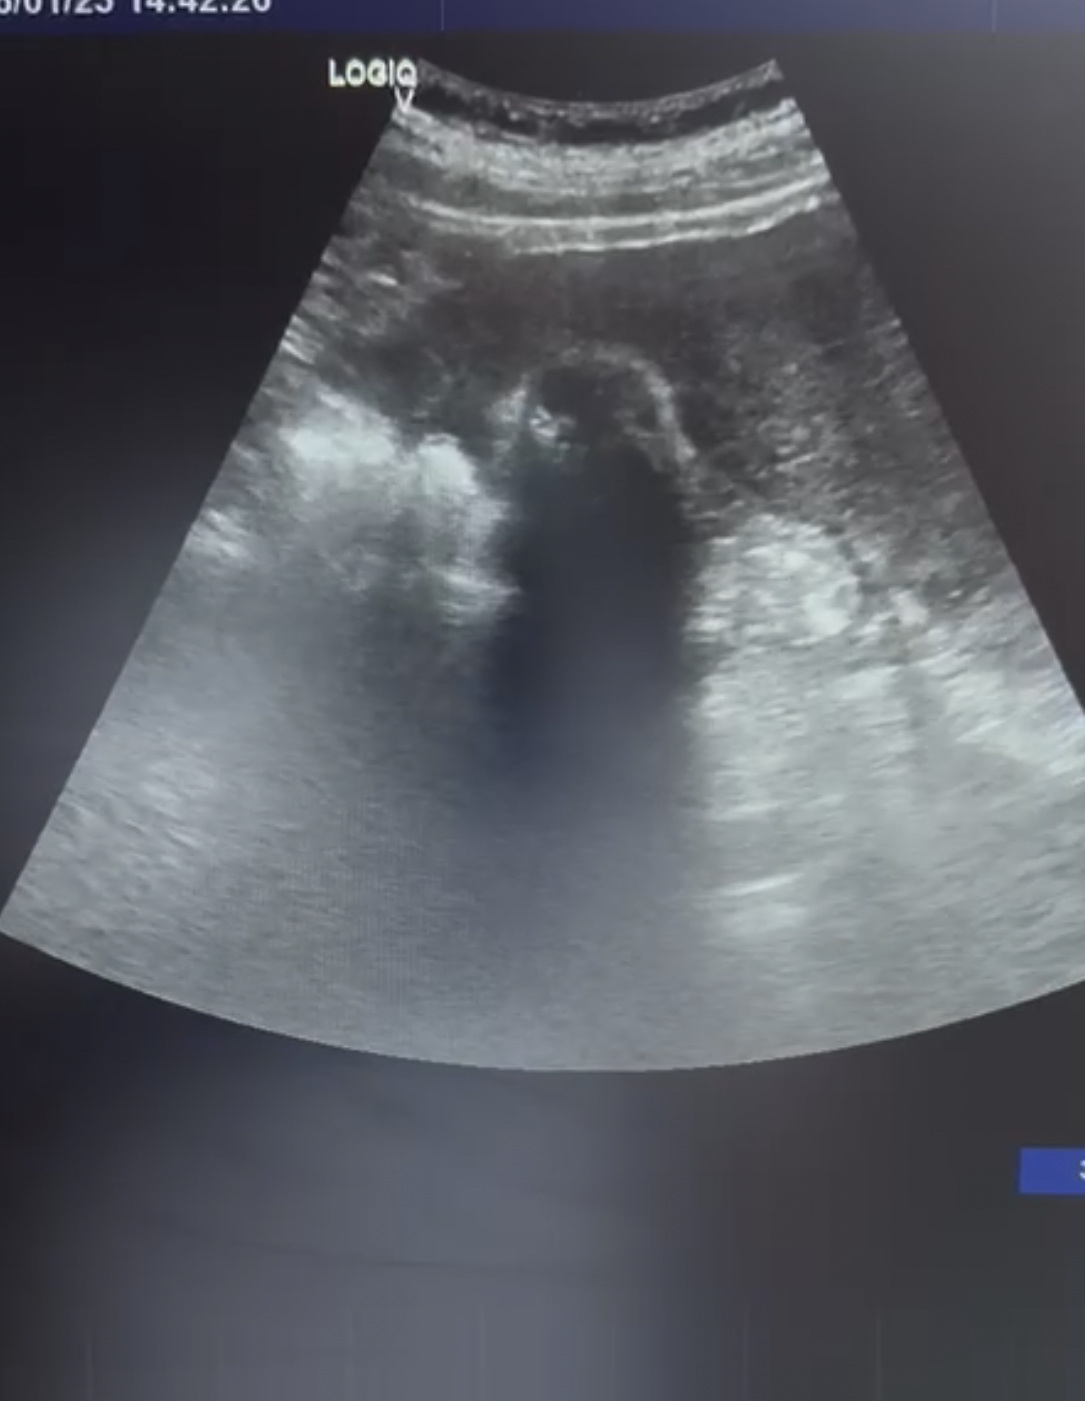

Hallazgos ecográficos

Se observa la vesícula biliar con varias litiasis en su interior y sombra acústica posterior. No se observan signos de colecistitis ni dilatacion de la vía biliar.